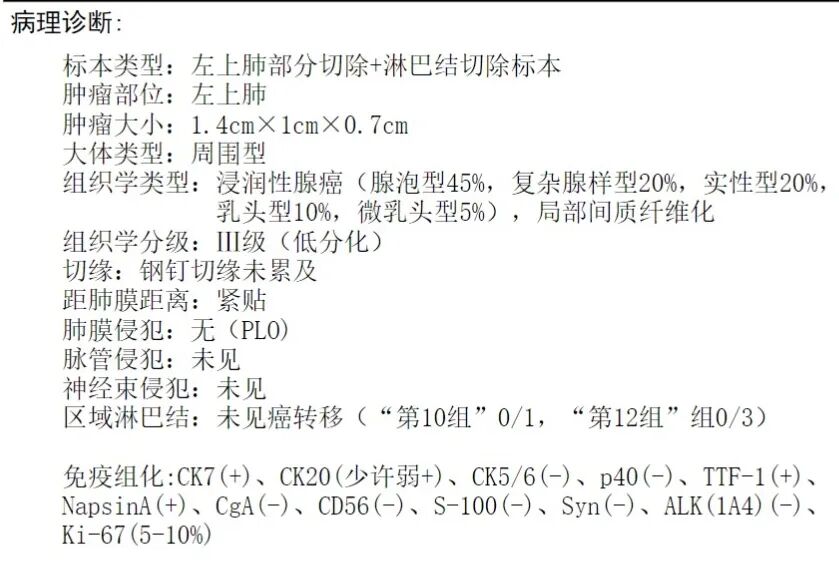

常规病理示:浸润性腺癌,腺泡型45%,复杂腺体20%,实性型20%、乳头型10%、微乳头5%,局部间质纤维化。长径1.4厘米,低分化。切缘阴性,紧贴胸膜,但未侵犯(PL0),未见脉管侵犯。第10组及第12组淋巴结未见转移(术中探查纵隔未见明显肿大淋巴结)。

感悟: